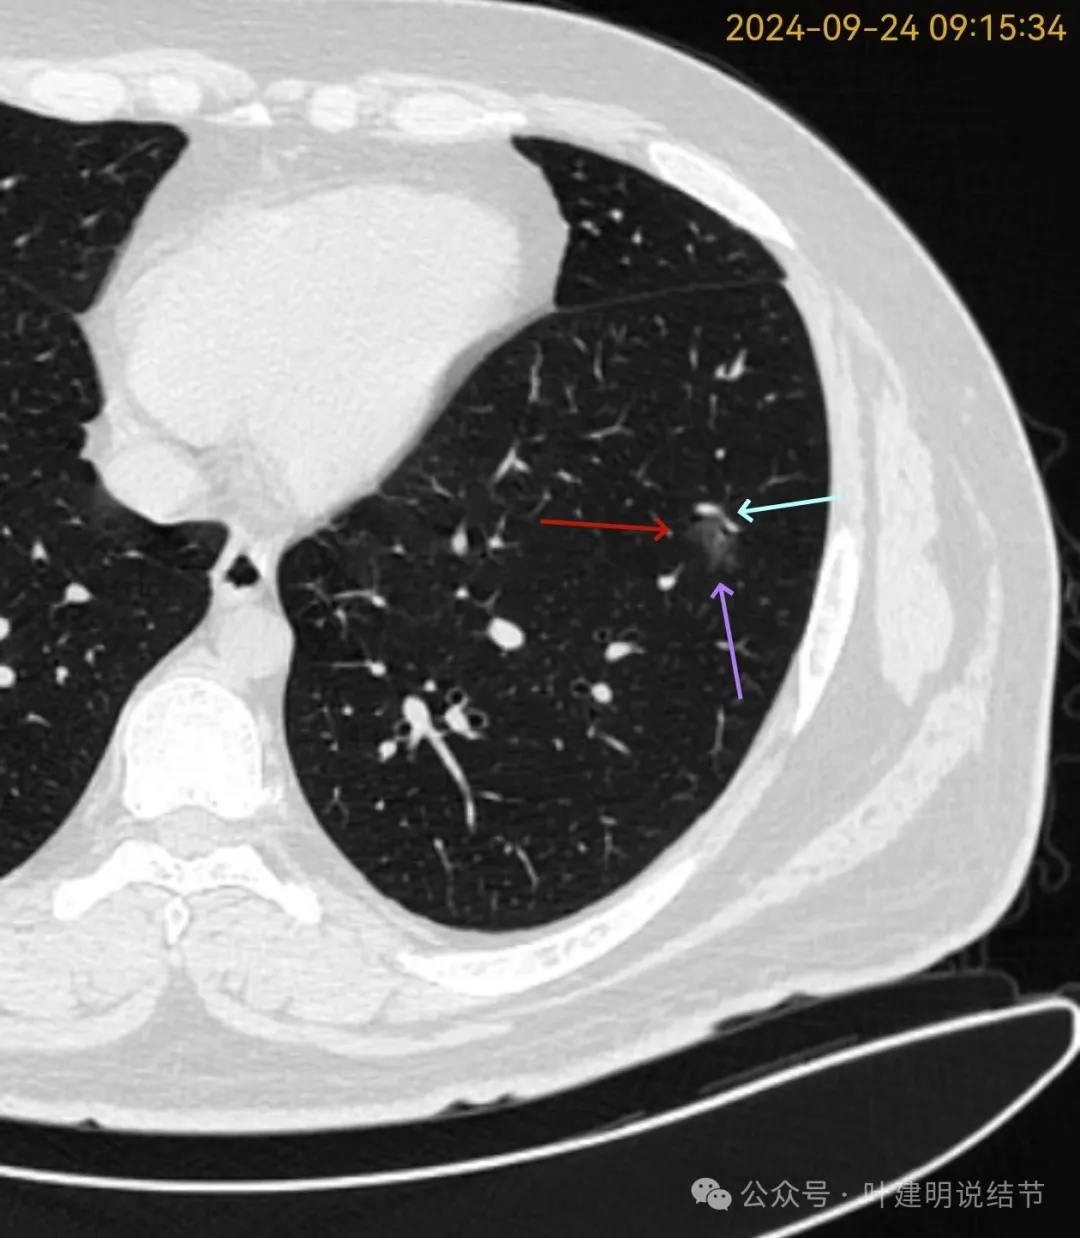

再看2024年9月复查的片子:

病灶出现,磨玻璃密度。有微小血管与细支气管通气征。

邻近细支气管扩张、边缘细毛刺、整体轮廓清。

有毛刺征,整体轮廓清,与血管之间间隙消失。

毛刺、血管征、邻近支气管扩张、整体轮廓清,病灶与血管间隙消失。

有少许偏实性成分,整体轮廓清。

纯磨密度,不太纯,血管贴边,血管与病灶间隙消失,整体轮廓与瘤肺边界清。

血管弯征可见、细毛刺明显、细支气管扩张,血管进入。

密度总体不高,轮廓与边界清楚。

密度较淡,轮廓较清。

边缘区密度淡且较纯,轮廓清楚。